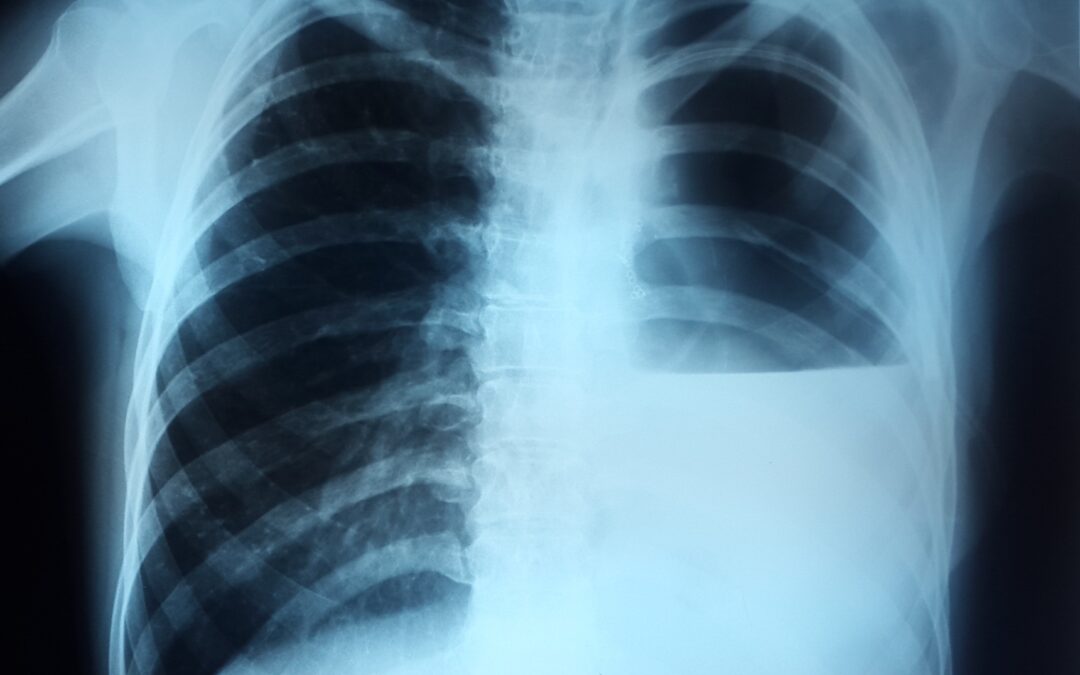

გიგანტური ბულის სარქვლოვანი ბრონქობლოკაცია პაციენტი 45 წ ქალბატონი. 2022 წ თებერვალში გადაიტანა კოვიდ – 19 მძიმე ფორმაში სტაციონარის რეანიმაციულ განყოფილებაში, სადაც უტარდებოდა ოქსიგენოთერაპია CPAP da BiPAP რეჟიმებში. გამოწერიდან მალევე გაუჩნდა ჰაერის...